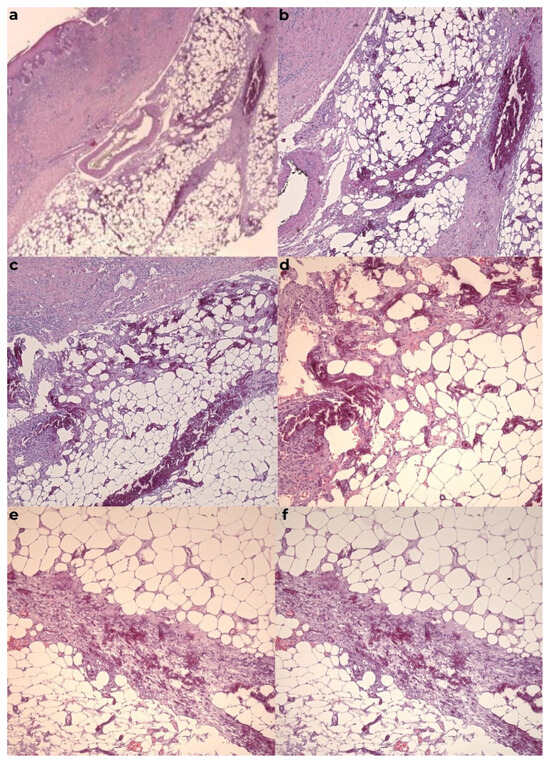

The histopathological examination confirmed the diagnosis of calciphylaxis, revealing a moderately infiltrated polymorphous inflammatory response in the dermis, marked by congestion and edema. The venous vessels in the deep dermis and subcutaneous tissue were dilated, with intraluminal fibrino-hemato-leukocytic thrombi, while the arterial vessels displayed thickened walls with intimal hyperplasia obstructing the lumen. Additionally, there was prominent sclero-hyalinosis in the subcutaneous tissue and delineating lobules of adipose tissue, with some exhibiting features of liponecrosis, along with isolated dystrophic calcifications. These morphological features were consistent with ischemic changes secondary to calciphylaxis. Routine hematoxylin-eosin staining, as well as special stains such as von Kossa, were performed (Figure 7 and Figure 8).

Figure 7. The calcified material was surrounded by multinucleate giant cells, often associated with psammoma-like calcifications. Calcium deposits were localized in the intima and media of the small and large vessels in the deep dermis and hypodermis and were frequently accompanied by vascular thrombi. Hemorrhages may have occurred in the subcutaneous adipose tissue, along with liponecrosis and chronic lymphoplasmacytic inflammatory infiltrates. Calcium deposits could also be observed in the fibrous septa of the subcutaneous adipose tissue. (a) HE×2.5, (b) HE×5, (c) HE×5 ob0001, (d) HE×10, (e) HE×10 ob0001, and (f) HE×10 ob0004.